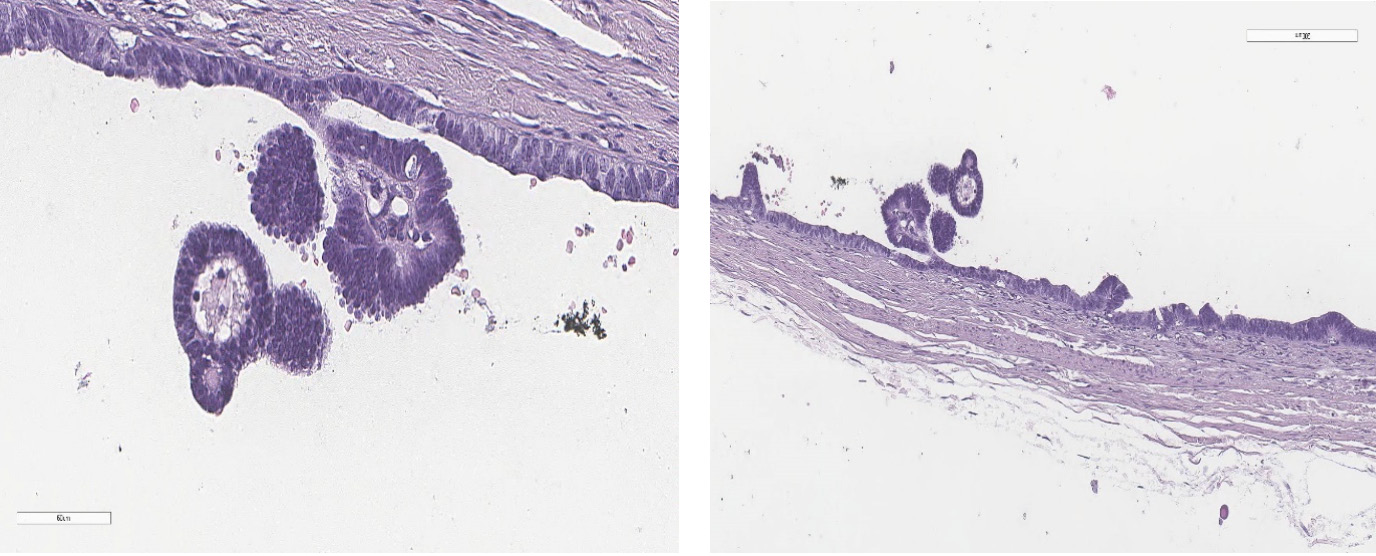

A histological examination of the excised appendages (see Fig. 2–9) revealed the concurrent presence of ovarian stroma and testicular tissue, consisting of tubules lined with Sertoli cells devoid of atypia and spermatogenesis, surrounded by Leydig cells. This finding suggests the presence of bilateral ovotestes. Fallopian tubes exhibited signs of hypoplasia, manifesting as a polycystic mass lined by a single layer of flattened tubal epithelium.

Fig. 3. Ovarian component of the ovotestis, consisting of fibroblasts. Hematoxylin and eosin staining, ×60

Fig. 4. Testicular component of the ovotestis, composed of seminiferous tubules lined with Sertoli cells without atypia and without spermatogenesis, along with areas of Leydig cells. Hematoxylin and eosin staining, ×60

Fig. 7. Ovarian component of the ovotestis, composed of fibroblasts with clusters of Leydig cells at the border with the testicular component. Hematoxylin and eosin staining, ×60

Fig. 8. Testicular component of the ovotestis, composed of seminiferous tubules lined with Sertoli cells without atypia and without spermatogenesis (A), surrounded by Leydig cells (B). Hematoxylin and eosin staining, ×200, ×60